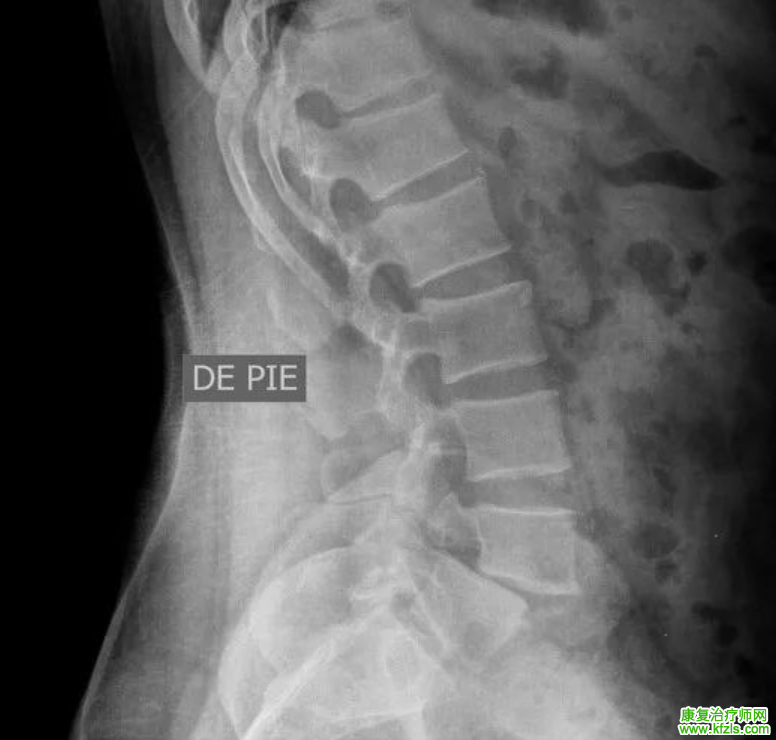

Ⅰ度

腰4椎弓峡部裂、腰4椎体向前 I 度滑脱